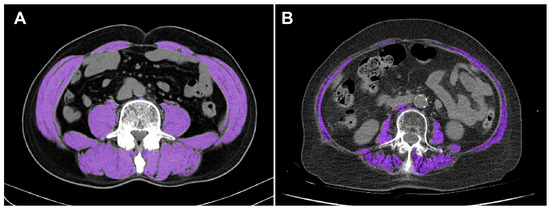

Impact of CT-Defined Sarcopenia on Clinical Outcomes in Elderly Trauma Patients: A Retrospective Korean Cohort Study

Background/Objectives: Sarcopenia, the age-related decline in skeletal muscle mass and function, is increasingly recognized as an important prognostic factor among elderly patients. This study aimed to evaluate whether computed tomography (CT)-defined sarcopenia independently predicts short-term mortality in elderly Korean trauma patients. Methods: We [...] Read more.

Background/Objectives: Sarcopenia, the age-related decline in skeletal muscle mass and function, is increasingly recognized as an important prognostic factor among elderly patients. This study aimed to evaluate whether computed tomography (CT)-defined sarcopenia independently predicts short-term mortality in elderly Korean trauma patients. Methods: We retrospectively analyzed 722 patients aged ≥65 years admitted to a Korean Level I trauma center between January 2020 and December 2021. Sarcopenia was defined as the lowest sex-specific quartile of skeletal muscle index (SMI) measured at the third lumbar vertebra (L3) within 7 days of admission. Demographics, injury severity, and outcome variables were compared between groups. Kaplan–Meier survival analysis with a 24 h landmark and multivariable Cox regression were applied to identify independent predictors of 30-day mortality. Results: Among 722 patients, 181 (25.1%) were sarcopenic. They were older and had lower body mass index and serum albumin yet showed lower Injury Severity Score (ISS) at presentation. Despite this, in-hospital mortality was higher in sarcopenic patients (15.5% vs. 9.8%, p = 0.036), while 24 h mortality did not differ (4.4% vs. 3.7%, p = 0.663). Landmark analysis starting at 24 h demonstrated significantly worse 30-day survival in the sarcopenia group (log-rank p = 0.028). Multivariable Cox regression confirmed sarcopenia as an independent predictor of 30-day mortality (HR, 2.36; 95% CI, 1.07–5.23; p = 0.034), along with higher ISS and lower Glasgow Coma Scale (GCS) scores. Conclusions: CT-defined sarcopenia at the L3 level independently predicts 30-day mortality in elderly trauma patients and may support early risk stratification. Full article